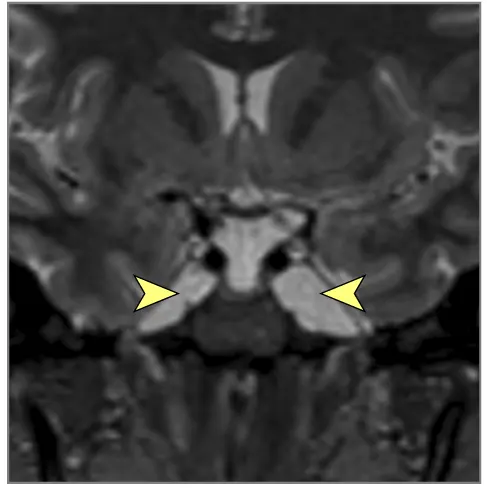

| ჰიდროცეფალია (ობსტრუქციული ან კომუნიკაციური, NPH-ის გამორიცხვით) | აწეული ICP-ის სიმპტომები: თავის ტკივილი, გულისრევა/ღებინება, პაპილედემა, CN VI პარეზი, ლეთარგია/შეცვლილი ცნობიერება. სიარულის/კოგნიტური ცვლილებები შესაძლებელია. დაწყება შეიძლება იყოს მწვავე (მაგ., წყალსადენის სტენოზი, სიმსივნის ბლოკირება) ან ქვემწვავე/ქრონიკული (SAH/მენინგიტის შემდგომ). | მრტ/კტ აჩვენებს პარკუჭების გადიდებას ხშირად ლიკვორის ობსტრუქციის ნიშნებით (მაგ., გაფართოებული საფეთქლის რქები, წყალსადენის შევიწროება) ან დაქვეითებული შეწოვით. LP გახსნის წნევა ტიპიურად მომატებულია. |

- თავის ტვინის მრტ: სასურველი მოდალობა დეტალური ანატომიური შეფასებისთვის. შეუძლია აჩვენოს პარკუჭების გადიდება (ჰიდროცეფალია), გამოავლინოს ობსტრუქციული დაზიანებები (სიმსივნეები, კისტები, წყალსადენის სტენოზი), აჩვენოს მომატებული ICP-ის გართულებები (თიაქარი), აღმოაჩინოს კომუნიკაციური ჰიდროცეფალიის მიზეზები (მაგ., წინა სისხლჩაქცევის/ინფექციის ნიშნები), გამოავლინოს IIH-ის მიმანიშნებელი ნიშნები (ცარიელი კეხი, მხედველობის ნერვის გარსის გაფართოება, უკანა თვალის კაკლის გაბრტყელება, ვენური სინუსის სტენოზი MRV-ზე), ან აჩვენოს ცერებრალური შეშუპების გამომწვევი ძირითადი პათოლოგია (ინსულტი, სიმსივნე, ანთება) (7). სპეციფიკურ მიმდევრობებს (მაგ., CISS/FIESTA) შეუძლიათ შეაფასონ ლიკვორის ნაკადის დინამიკა.

- თავის ტვინის კტ: უფრო სწრაფი და ხელმისაწვდომი, შესანიშნავია გადაუდებელ სიტუაციებში მწვავე სისხლჩაქცევის, ჰიდროცეფალიის (პარკუჭის ზომა, პერივენტრიკულური გამჭვირვალობა, რაც მიუთითებს ტრანსეპენდიმურ შეშუპებაზე), დიდი მასების ან თავის ქალას მოტეხილობების აღმოსაჩენად. ნაკლებად მგრძნობიარეა ვიდრე მრტ დახვეწილი სტრუქტურული დაზიანებების, უკანა ფოსოს პათოლოგიის ან IIH-ის სპეციფიკური ნიშნებისთვის.